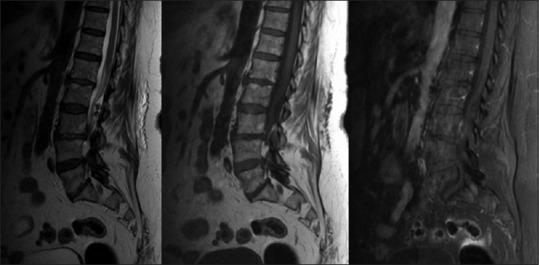

We present the case of a 72-year-old female who had longstanding history of low back pain that exacerbated 20 days prior to the presentation to the emergency room with a frank cauda equina syndrome. The lumbar computed tomography scan showed a hyperdense lesion, suggestive of calcified tumor, whereas the magnetic resonance imaging revealed a hypointense lesion on theT1 and T2-weighted images, without contrast enhancement or edema on fluid-attenuated inversion recovery. She underwent an emergent L2-L4 laminectomy and L3-L4 discectomy with resection of L2 intradural tumor, following which she regained normal function.

我们报告一例72岁女性,有长期腰痛病史,在因明显的马尾神经综合征就诊于急诊室前20天病情加重。腰椎计算机断层扫描显示高密度病变,提示钙化肿瘤,而磁共振成像在T1加权和T2加权图像上显示低信号病变,在液体衰减反转恢复序列上无强化或水肿。她接受了急诊L2-L4椎板切除术和L3-L4椎间盘切除术,并切除了L2硬膜内肿瘤,术后恢复了正常功能。